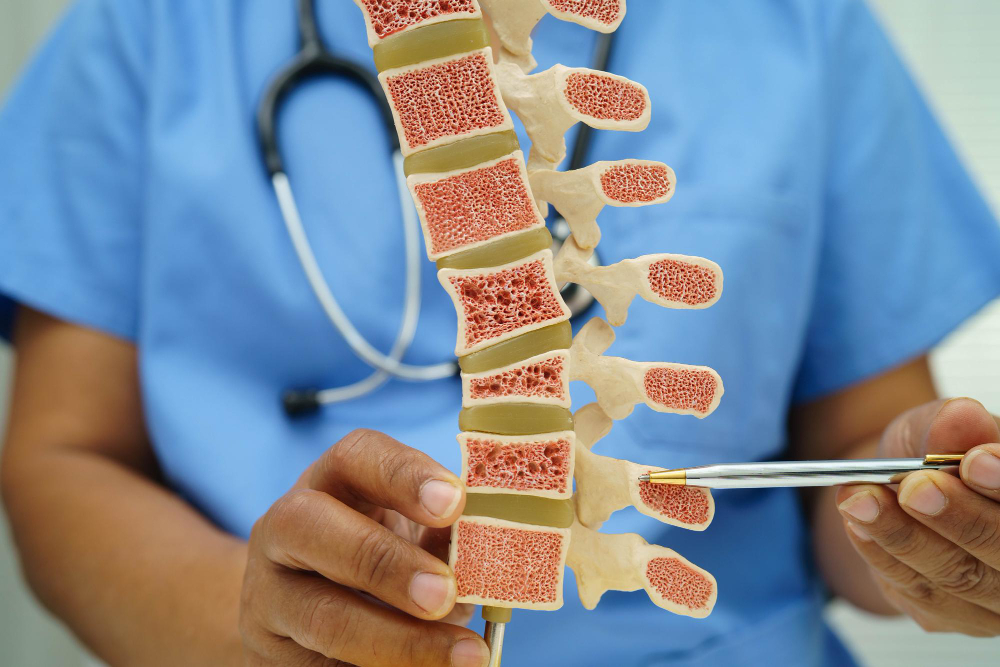

What is a Herniated Disc? A herniated disc happens when the soft center of a spinal disc pushes out through a crack in the tougher outer layer. This can press o

Bone health is vital at every age. Many people think only the elderly need to worry about bones, but that’s far from the truth. Everyone

Back pain is becoming more common, especially in India’s busy cities. People are leading more sedentary lifestyles, which can lead to spinal problems. One such